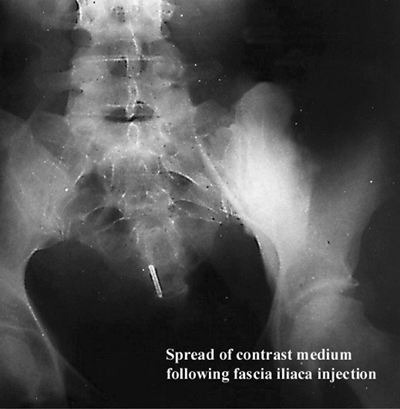

The psoas muscle surrounded by the fascia iliaca and its extensions,

the femoral, lateral cutaneous, and obturator nerves, which run

immediately under the fascia iliaca. When the local anesthetic is

injected under the fascia, the diffusion can theoretically reach the

three nerves (Fig. 28-3).